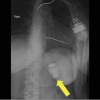

Introduction: Obesity levels mean an increased presentation of patients with Laparoscopic adjustable gastric banding (LAGB). Method: Literature search revealed a paucity of information on ultrasonography to diagnose a slipped LAGB. Conclusion: 2D Ultrasonography with a standard low frequency curvilinear probe proved to be a simple, effective method of diagnosing slipped Laparoscopic adjustable gastric banding (LAGB). We suggest the inclusion of routine abdominal ultrasound (after drinking water to improve sensitivity of the test) as part of the routine workup of suspected LAGB slippage.